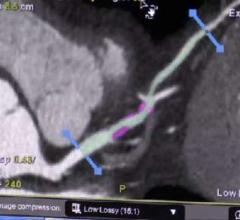

DAIC/ITN editor Dave Fornell shows some of the most innovative new cardiac CT and angiography technologies from sessions ...

An interview with Matthew Budoff, M.D., FACC, director of cardiac CT, Harbor-UCLA Medical Center, Torrance, Calif., at ...

An interview with Ricardo Cury, M.D., director of cardiac imaging, Miami Cardiac and Vascular Institute, at the Society ...